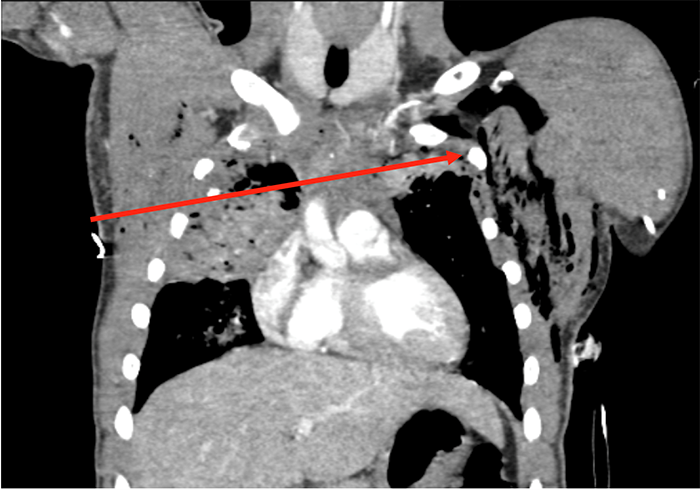

Given his clinical stability, we opted to send our patient for chest CT with intravenous contrast, which revealed a comminuted right second rib fracture, right upper lung contusion with trace right hemopneumothorax, anterior mediastinal hematoma, and left upper lung contusion with left hemothorax. There was no evidence of great vessel injury, active extravasation or pericardial effusion. The bullet was located much more inferiorly, in the left diaphragmatic sulcus at the left lung base. We believe that the bullet traversed both lungs and the superior anterior mediastinum (see red lines in Figure 2 and Figure 3), striking the left second rib and coming to rest in the pleural space along this trajectory. From there, the bullet apparently moved dependently within the pleural space and came to rest in the posterior sulcus.

Figure 2. Coronal CT image of patient with Transmediastinal gunshot wound. Solid red line depicts bullet trajectory based on tissue injury on CT scan.

The patient was taken urgently to the operating room for further evaluation, as the CT findings did not guarantee a linear bullet trajectory across the anterior mediastinum superior to the heart and did not definitively rule out cardiac, esophageal, or tracheobronchial injuries. Despite his negative FAST exam, the patient's bilateral hemothoraces raised the possibility of an occult cardiac injury decompressing into his pleural spaces (Figure 4).